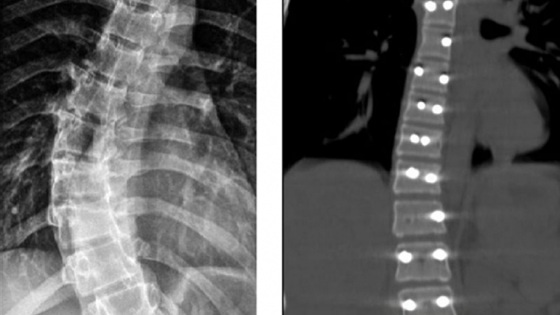

На этот раз медицинская помощь потребовалась 14-летней пациентке, страдающей идиопатическим сколиозом. У нее было диагностировано искривление позвоночника под углом в 40 градусов. Такая деформация со временем могла негативно сказаться на функционировании сердца и легких. Медики приняли решение о проведении операции с целью остановить прогрессирование заболевания и вернуть позвоночнику правильное положение.

В ходе оперативного вмешательства девочке была установлена прочная металлическая конструкция, обеспечивающая фиксацию позвоночника в выпрямленном положении. После операции пациентка быстро восстановилась и была выписана из больницы.